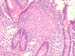

Therapeutic strategies for control of intestinal inflammation in patients with Crohn's disease (CD) are mostly pharmacological. The introduction of biological therapies, in particular, has changed the management of CD considerably and enabled a shift in therapeutic goals from control of symptomatic disease to control of inflammation itself, with endoscopic mucosal healing being a major target of disease treatment. Since inflammation in CD is complex with many pathways identified, there has been no shortage of candidate factors or methodologies to inhibit or promote the inflammatory process. However, despite such progress, therapies that directly target cells or factors involved in the inflammatory process are suppressive at best and lead to mucosal healing in a minority of patients.

Exclusive enteral nutrition (EEN) is best described as the provision of nutritionally complete liquid formula, without exposure to other foods, to patients with CD, usually for 6–8 weeks.[1] Its success in inducing both clinical remission and intestinal mucosal healing in a high proportion of patients with active inflammatory CD represents a major paradigm shift in approach.[2,3] Why it works has baffled the IBD scientific community who have tried to fit the effects of EEN into the currently held views on the pathogenesis of CD that are at best vague, summed up as 'a complex interplay between genetic predisposition, environmental factors, the gut microbiota and the host immune system'.[4] The impact of EEN has not only been on the patients, but also on the research community who are earnestly searching for 'real food' dietary interventions that might emulate the efficacy of EEN without such a degree of restriction. This effort goes hand-in-hand with attempts to identify dietary factors that might lead to or protect from the development of CD, with the view that such factors might also be involved in perpetuating disease once it has developed. Specific dietary factors and/or dietary patterns, are reviewed in detail elsewhere.[5] Contrary to such concepts, presumed protective factors (fibre and docosahexaenoic acid) are rarely present in EEN formula[6] and components implicated by some in CD development or progression (such as emulsifiers and maltodextrin) are present in EEN formula,[6] often in doses higher than that found in food.[7] These somewhat contradictory concepts raise questions around our current understanding of the pathogenesis of CD.